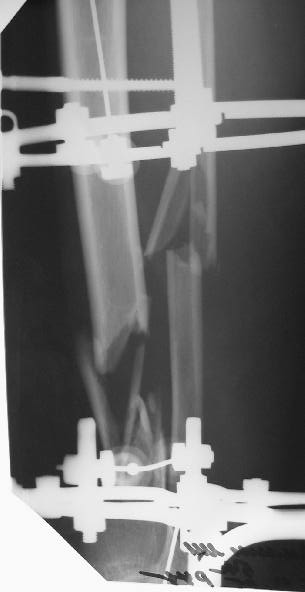

Больного прооперировал, обработку мягких тканей на голени не стал делать, думаю, некроз по краю швов на голени заживет под струпом (рис 3). На стопе удалил некротические ткани, готовлю ее к аутопластике (рис 2).

На дополнительных снимках итраоперационно видна значительная потеря массы (рис 6 рис 1). Хотя на снимках контрольных после операции вроде дефекта значительного нет. Все же придется, как-то замещать дефект костный на голени, думаю подготовить морально больного к повторной операции костной пластике, после заживления ран.